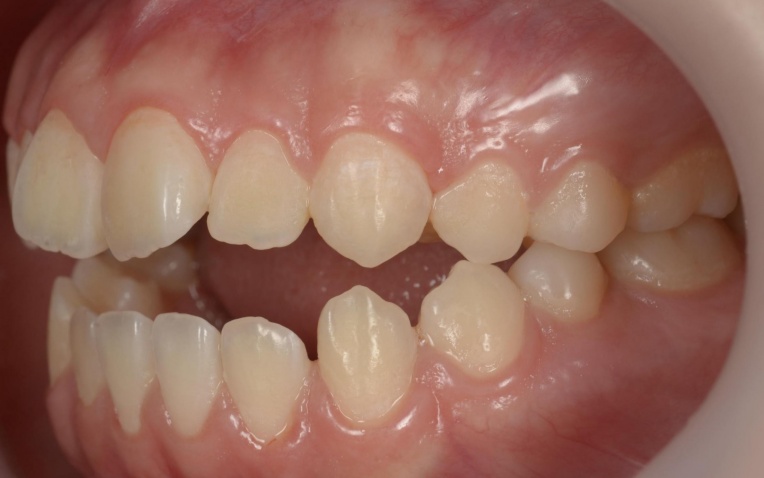

「前歯が噛み合わないので治したい」とご相談いただきました。 |

拝見したところ、重度の開咬(かいこう)が認められました。 |